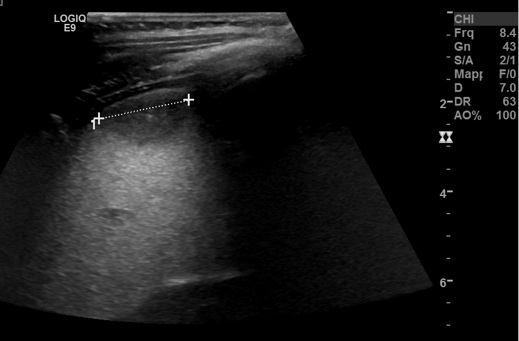

ingranditi ovalariformi.� Figura 4. L�RMN evidenzia nella

milza micro alterazioni diffuse, con due lesioni maggiori con una

regione a bersaglio perilesionale. Tale atteggiamento potrebbe anche

essere espressione di attecchimenti ascessuali.

linfonodo superficiale palpabile. La RMN (Figura 4) evidenzia �nella

essere espressione di attecchimenti ascessuali.�